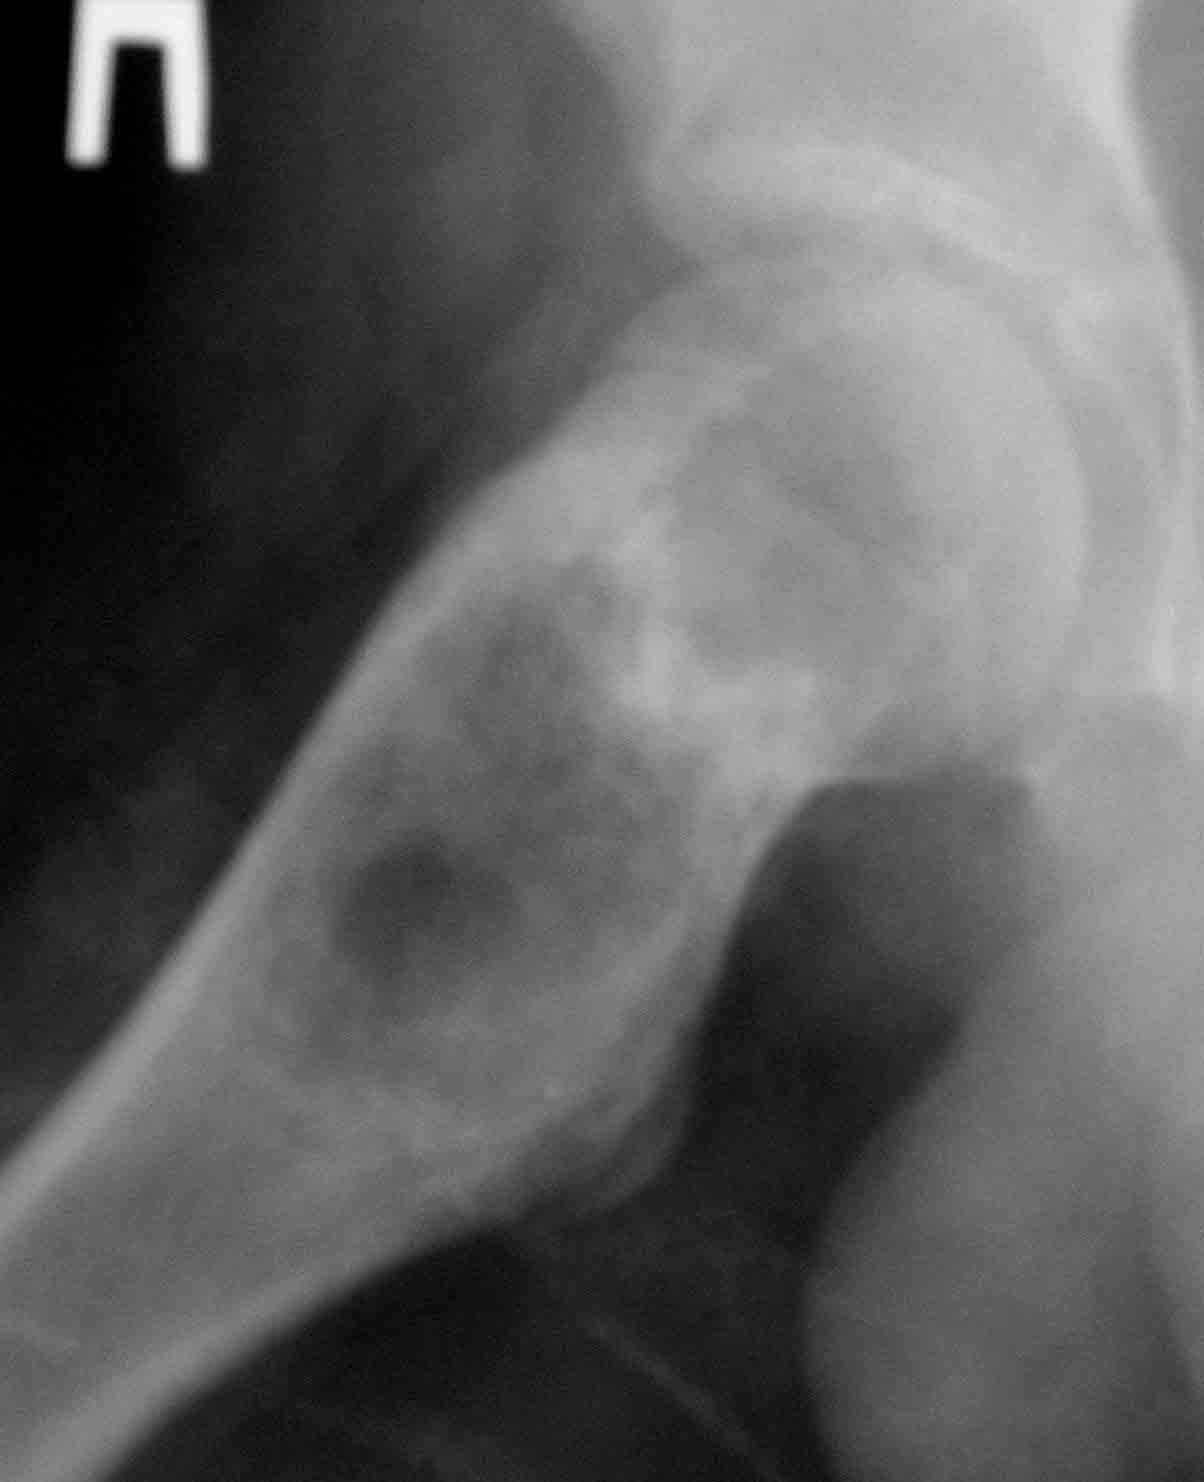

Дабы не уводить в офтопик вопрос о несросшемся переломе бедра, хочу добрым словом упомянутьколлапан - доступный и эффективный российский продукт, который судя по публикациям на форуме не нашел еще должного распространения в повседневной практике. Чтобы не быть обвиненным в рекламе или личной заинтересованности скажу, что работаю я в Казахстане, где большинство последних российских разработок не прошло регистрацию( отдельный вопрос почему?) и коллапан завозят родственники пациентов из соседних сибирских городов. За тридцать лет практики многократно возникали ситуации в которых остро чувствовалась проблема материала для заполнения костных дефектов- от открытых переломов до дефектов при секвестрэктомиии и удаления кистозных опухолей. Риск аутопластики в инфицированную среду или дефицит донорской кости у детей, повсеместное закрытие лабораторий консервации тканей, высокая стоимость зарубежных остеоиндуктивных материалов делают коллапан одним самых доступных материалов в exUSSR \простите за пафос\. В нашем отделении мы применяем коллапан в гранулах с антибиотиком для пристеночной пластики при удалении секвестров при послеоперационных и посттравматических остеитах, при остеосинтезе ложных суставов и заполнении костных дефектов. Коллапан не может применяться в ситуациях где имплантату необходима опорная функция, но это уже другая песня. Привожу пример 15 летнего пациента с обширной фиброзной дисплазией проксимального бедра, которого я оперирован в ноябре 2005, контрольный снимок от 3-2006.

Произведена подвертельная трепанация, кюретаж и рыхлое заполнение гранулами коллапанаГ полости, ушло до 100 куб см гранул. Иммобилизация не проводилась, нагрузка на ногу разрешения через 5 мес, сейчас подросток активно отдыхает на каникулах. Аваскулярный некроз головки вроде не предвидится, думается, что в процессе роста кисты коллатеральное кровообращение сформироваласьдостаточно, о судьбе ростковой зоны можно будет говорить через год. Кстати в одном НИИ ему былапредложена операция эндопротезирования. Первые 2 мес